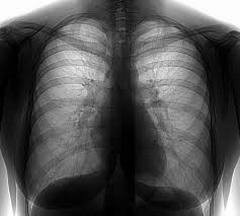

Флюорография легких представляет собой исследование органов грудной клетки при помощи рентгеновских лучей, которые проникают через легочную ткань и переносят рисунок легких на пленку. Данную процедуру назначают лицам старше восемнадцати лет. Плановая флюорография не должна проводиться чаще одного раза в год. Это исследование дает возможность выявить патологические изменения в органах грудной клетки.

Так как органы грудной клетки поглощают излучение по-разному, снимок выглядит неоднородным. Бронхиолы, бронхи и сердце на снимке отображаются светлыми пятнами. Если у человека здоровые легкие, то флюорография отобразит легочную ткань равномерной и однородной.